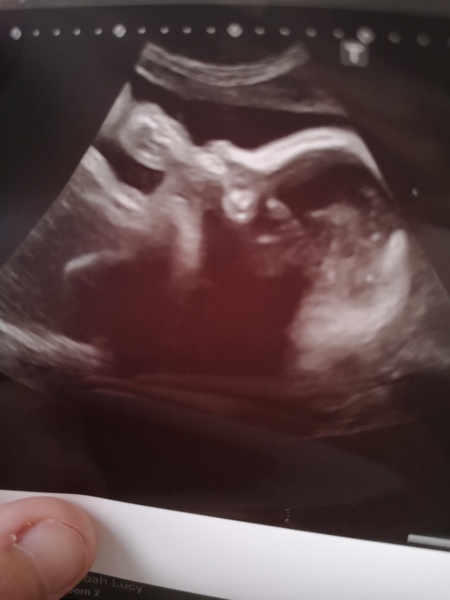

Growth scan done. Girl is estimated 4lb 15 and boy is 5lb 15, so I have just under 11lbs of baby in my petite size 8 frame 😆

Girl has gone from 50th centile down to 10th so they had urgent call with the consultant who said to give me the steroid injection, 2nd one due tomorrow and they will more than likely bring the csection date forward now. I also had the MRSA screening which basically I just had to swab my nostril and another swab in my groin.

Finally managed to see one of their faces, they have been very stubborn at every scan before now, so this is twin 2 - boy sucking his thumb! 😍 Shit just got very real for me.